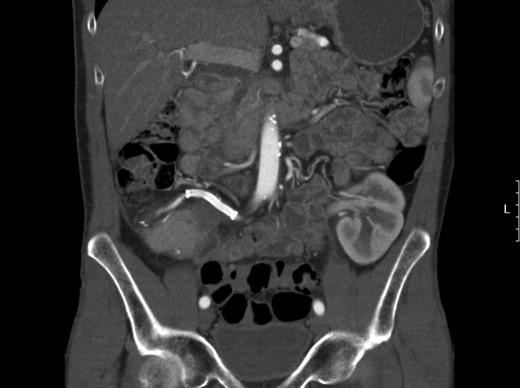

Eventually the patient recovered and could be discharged in good condition. An outpatient follow-up CT, however, showed an aneurysm of the pancreatic graft’s arterial reconstruction, most likely at the site of the anastomosis of the iliac Y graft with the splenic artery (Fig. 2), with the peripancreatic abscess as the most likely cause. Because of its size and growth, consent was given for removal of the pancreas, with subsequent pancreatic islet isolation and transplantation to retain beta cell function.

Elective CT scan showing pseudoaneurysm of the vascular reconstruction, most likely at the site of the anastomosis between Y graft and splenic artery.